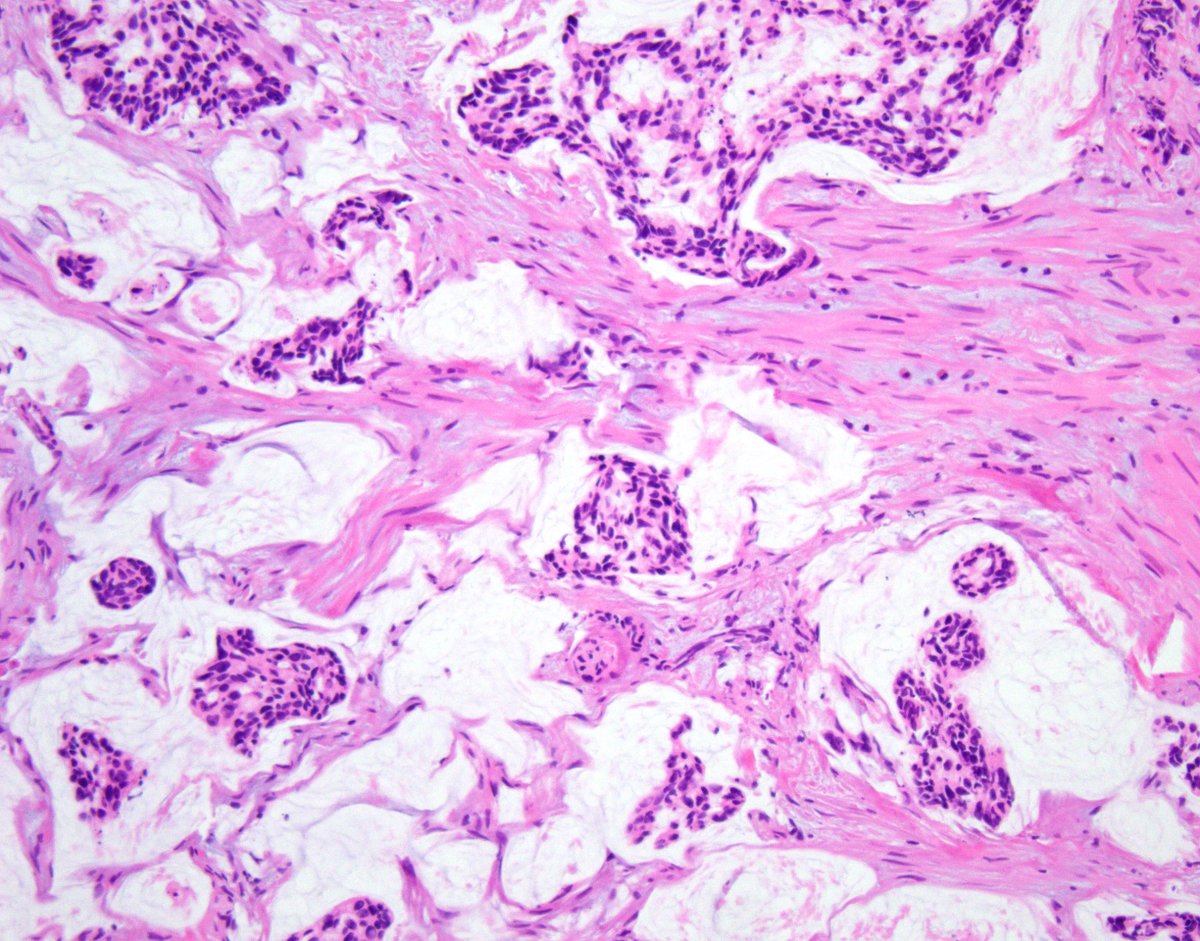

@GladellPaner

Tubulocystic renal tumor with a twist. 👀 What’s your top diagnosis #GUPath tweeps? #OnePicDx Answer in comment. 👇🏻👇🏻👇🏻

3

28

118